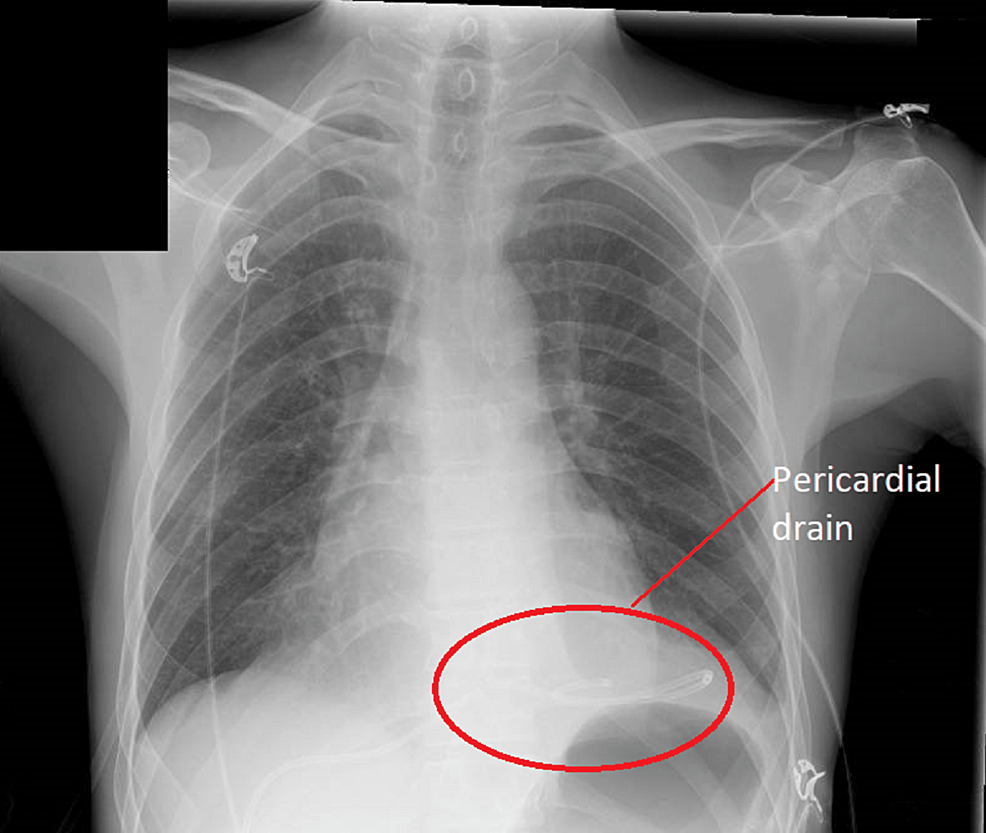

Chest X-Ray For Pericardial Effusion . the most sensitive sign for a pericardial effusion on cxr is enlargement of the cardiac silhouette (cardiothoracic ratio. Computed tomography (ct) and magnetic. pericardial effusion is present when the fluid in the pericardial space exceeds its physiological amount (≤50. a pericardial effusion is considered to be present when accumulated fluid within the sac exceeds the small. the chest radiograph may not directly identify a pericardial effusion.